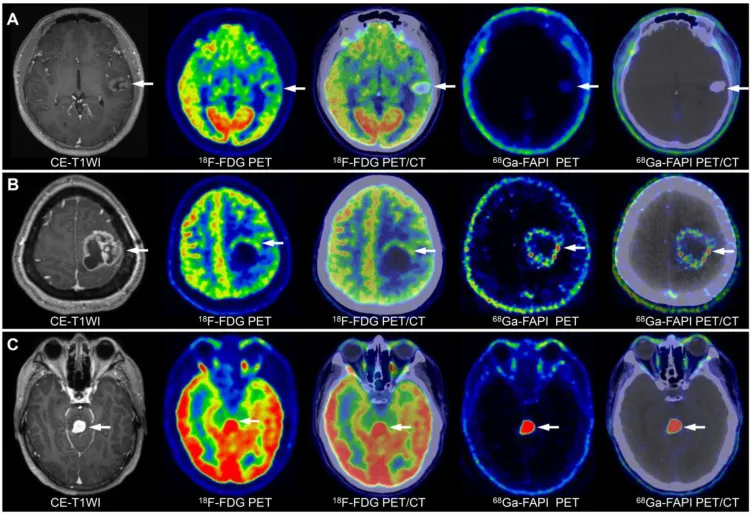

不同级别胶质瘤影像特征显示:A为低级别胶质瘤;B为三级胶质瘤;C为四级胶质瘤。

重要的是,PET已被证明是引导立体定向活检规划的重要成像方式。适当的目标选择对获取能准确指导后续管理的代表性组织样本至关重要。使用PET示踪剂可识别肿瘤中代谢活跃、含有高度增殖细胞的区域,为组织病理学分析提供最佳样本。然而,PET引导活检的主要局限是肿瘤需足够大才能被PET检测到(即直径>0.7cm),且需根据化合物半衰期协调示踪剂注射和扫描采集时间。